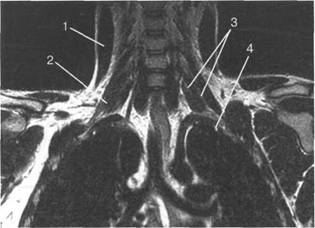

Cv.

Поперечные размеры составляют 30x20 мм, высота - 30-40 мм.